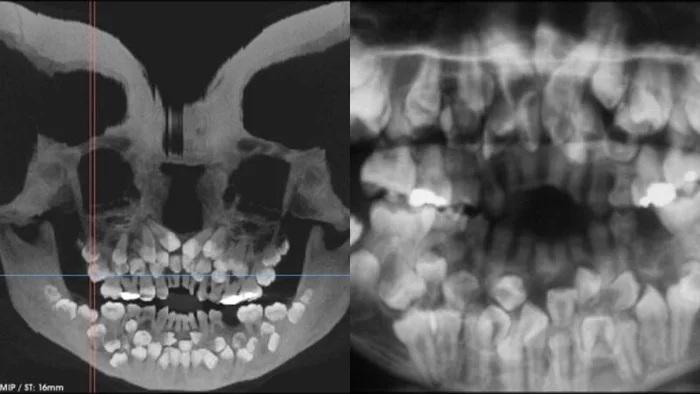

Sự việc bắt đầu khi một bé gái 11 tuổi 8 tháng tuổi đến phòng khám nha khoa ở Minas Gerais, Brazil, với mong muốn nhổ bỏ hàng răng sữa trên cùng vẫn chưa rụng. Tuy nhiên, kết quả chụp X-quang đã hé lộ một sự thật không ngờ: tổng cộng có 18 răng sữa, 32 răng vĩnh viễn và đáng kinh ngạc là 31 chiếc răng thừa ẩn sâu bên trong hàm.

Khi thăm khám ban đầu, các bác sĩ nhận thấy chỉ có 5 răng vĩnh viễn đã mọc, trong khi phần lớn răng sữa vẫn còn nguyên vẹn. Để có cái nhìn toàn diện hơn về tình trạng răng miệng của bệnh nhân, bác sĩ đã chỉ định chụp X-quang tổng quát và chụp sọ nghiêng. Những hình ảnh này không chỉ xác nhận số lượng răng bất thường mà còn cho thấy nhiều răng bị biến dạng và nằm sâu trong nướu, khiến việc phân biệt giữa răng bình thường và răng thừa trở nên vô cùng khó khăn.

Nhóm nghiên cứu từ Bệnh viện Nha khoa thuộc Đại học Liên bang Huesca ở Brazil đã công bố chi tiết về trường hợp đặc biệt này trên Tạp chí của Viện Hàn lâm Chỉnh nha và Phẫu thuật Miệng và Hàm mặt Hoa Kỳ. Để tìm hiểu nguyên nhân, các nhà nghiên cứu đã sử dụng hình ảnh chính xác để xác định vị trí răng và tiến hành xét nghiệm di truyền. Kết quả xét nghiệm nhiễm sắc thể cho thấy bé gái này có một đột biến gen hiếm gặp. Tuy nhiên, mối liên hệ nhân quả trực tiếp giữa đột biến gen và tình trạng đa răng vẫn cần được làm sáng tỏ thêm.